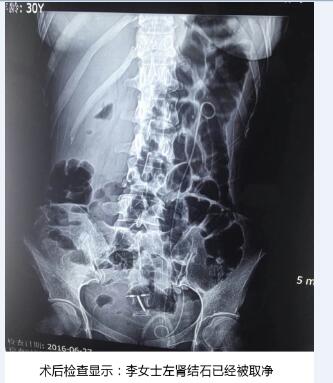

在天津百信医院结石病诊疗首席医生丁德刚主任的带领下,经过医生组周密讨论和精心会诊,一致认为该手术对医生技术和设备要求很高。如果对肾脏结构把握不好,容易造成术中出血量多,肾脏损伤大。终决定为李女士实施PCN+EMS术式(经皮肾镜联合超声碎石取石术)。从天津百信医院结石病诊疗首席医生丁德刚主任口中得知,该术大的优势——利用超声碎石清石系统将结石击碎吸出,再利用等渗盐水冲洗,冲出微小结石碎块,术中患者出血很少,手术非常。术后检查结果显示,取石率达到100%。

经过1个半小时手术,将李女士体内“心形”结石清除干净,手术非常顺利。

术后第二天早上9点,丁德刚主任医师就带领着医生组查房,得知结石已经取干净,李女士显得十分高兴,病房中不时传出爽朗的笑声。丁德刚主任还提醒道:术后经查已无结石残留,且术后恢复很不错,五天后便可出院。以后不管工作有多忙,一定要记得喝水,才能保证泌尿系统正常自我清洁。